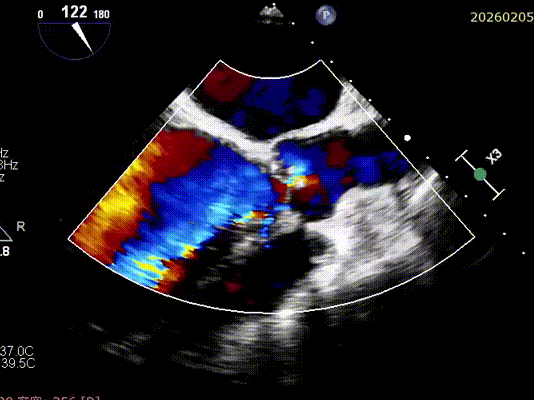

2026年伊始,TaurusTrio经导管主动脉瓣系统在复旦大学附属中山医院,浙江大学医学院附属第二医院,中国医学科学院阜外医院,首都医科大学附属北京安贞医院,四川大学华西医院等多家临床中心成功开展上市后全国首批植入。这不仅是TaurusTrio正式走向广泛临床应用的重要里程碑,更标志着中国单纯主动脉瓣反流介入治疗正式迈入了“心键合璧”的全新纪元。